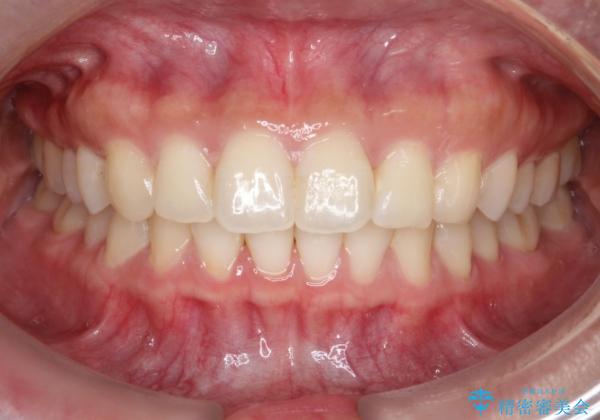

【インビザライン】翼状捻転+出っ歯を治したい

- 前歯の捻れと口元の突出を主訴に来院されました。

インビザラインを用いて上顎の遠心移動を行い、前歯を下げながら凸凹を綺麗に治すことができました。

歯を抜かない矯正治療を行う場合、口元は極端には変わりません。

今回は奥歯の遠心移動を行い、できる限り前歯を下げられるように治療を行いました。